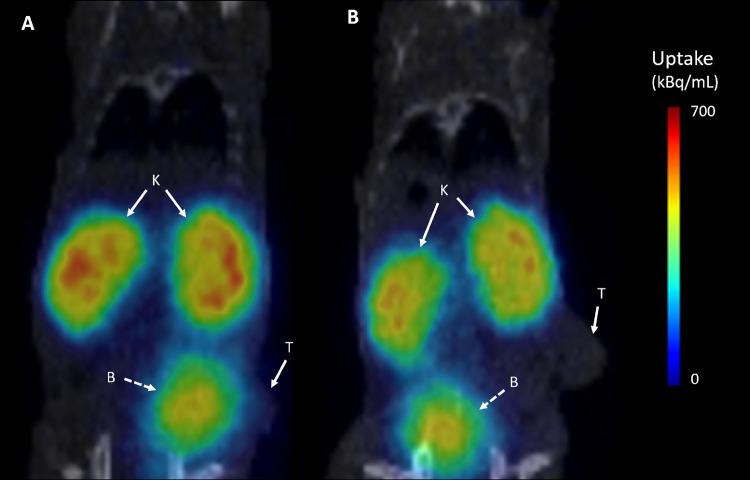

Neurotensin receptor 2 (NTS) is a well-known mediator of central opioid-independent analgesia. Seminal studies have highlighted NTS overexpression in a variety of tumors including prostate cancer, pancreas adenocarcinoma, and breast cancer. Herein, we describe the first radiometalated neurotensin analogue targeting NTS. JMV 7488 (DOTA-(βAla)-Lys-Lys-Pro-(D)Trp-Ile-TMSAla-OH) was prepared using solid-phase peptide synthesis, then purified, radiolabeled with Ga and In, and investigated on HT-29 cells and MCF-7 cells, respectively, and on HT-29 xenografts. [Ga]Ga-JMV 7488 and [In]In-JMV 7488 were quite hydrophilic (logD = -3.1 ± 0.2 and -2.7 ± 0.2, respectively, < 0.0001). Saturation binding studies showed good affinity toward NTS ( = 38 ± 17 nM for [Ga]Ga-JMV 7488 on HT-29 and 36 ± 10 nM on MCF-7 cells; = 36 ± 4 nM for [In]In-JMV 7488 on HT-29 and 46 ± 1 nM on MCF-7 cells) and good selectivity (no NTS binding up to 500 nM). On cell-based evaluation, [Ga]Ga-JMV 7488 and [In]In-JMV 7488 showed high and fast NTS-mediated internalization of 24 ± 5 and 25 ± 11% at 1 h for [In]In-JMV 7488, respectively, along with low NTS-membrane binding (<8%). Efflux was as high as 66 ± 9% at 45 min for [Ga]Ga-JMV 7488 on HT-29 and increased for [In]In-JMV 7488 up to 73 ± 16% on HT-29 and 78 ± 9% on MCF-7 cells at 2 h. Maximum intracellular calcium mobilization of JMV 7488 was 91 ± 11% to that of levocabastine, a known NTS agonist on HT-29 cells demonstrating the agonist behavior of JMV 7488. In nude mice bearing HT-29 xenograft, [Ga]Ga-JMV 7488 showed a moderate but promising significant tumor uptake in biodistribution studies that competes well with other nonmetalated radiotracers targeting NTS. Significant uptake was also depicted in lungs. Interestingly, mice prostate also demonstrated [Ga]Ga-JMV 7488 uptake although the mechanism was not NTS-mediated.

神经降压素受体2(NTS)是中枢性非阿片类镇痛的一种著名介质。开创性研究强调了NTS在包括前列腺癌、胰腺腺癌和乳腺癌在内的多种肿瘤中的过表达。在此,我们描述了首个靶向NTS的放射性金属化神经降压素类似物。JMV 7488(DOTA-(βAla)-Lys-Lys-Pro-(D)Trp-Ile-TMSAla-OH)采用固相肽合成法制备,然后进行纯化,用镓和铟进行放射性标记,并分别在HT-29细胞和MCF-7细胞以及HT-29异种移植瘤上进行研究。[Ga]Ga-JMV 7488和[In]In-JMV 7488具有很强的亲水性(logD分别为-3.1±0.2和-2.7±0.2,P<0.0001)。饱和结合研究表明其对NTS具有良好的亲和力([Ga]Ga-JMV 7488在HT-29细胞上的KD为38±17 nM,在MCF-7细胞上为36±10 nM;[In]In-JMV 7488在HT-29细胞上的KD为36±4 nM,在MCF-7细胞上为46±1 nM)和良好的选择性(高达500 nM时无NTS结合)。在基于细胞的评估中,[Ga]Ga-JMV 7488和[In]In-JMV 7488在1小时时分别显示出24±5%和25±11%的由NTS介导的高且快速的内化,同时NTS与膜的结合较低(<8%)。对于[Ga]Ga-JMV 7488,在HT-29细胞上45分钟时的外排高达66±9%,对于[In]In-JMV 7488,在HT-29细胞上2小时时外排增加至73±16%,在MCF-7细胞上为78±9%。JMV 7488的最大细胞内钙动员与左卡巴斯汀(一种已知的HT-29细胞NTS激动剂)相比为91±11%,证明了JMV 7488的激动剂行为。在携带HT-29异种移植瘤的裸鼠中,[Ga]Ga-JMV 7488在生物分布研究中显示出中等但有前景的显著肿瘤摄取,与其他靶向NTS的非金属化放射性示踪剂竞争良好。在肺中也观察到显著摄取。有趣的是,小鼠前列腺也显示出[Ga]Ga-JMV 7488摄取,尽管其机制不是由NTS介导的。